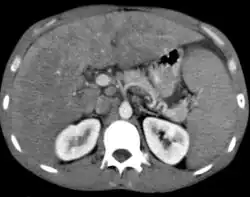

Micrograph of mantle cell lymphoma, a type of non-Hodgkin lymphoma. Terminal ileum. H&E stain.